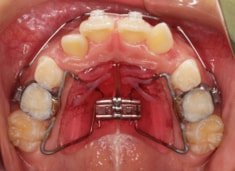

治療法:上顎急速拡大装置+クリアスナップ+フェイスマスク+上顎3番は開窓牽引CT写真にて位置確認

(難症例のため、小児期の矯正を2段階に設定しました)

骨年齢は実年齢よりも低めなので、今後下顎の旺盛な成長が見込まれます。

検査時のレントゲン分析では、上下顎の関係は、上顎の劣成長があり下顎前突傾向という値がでておりましたが、前歯ジャンプ後はフェイスマスクの効果もあり、上下顎の関係は正常化しています。

上顎が若干優位になっていますので、今後の下顎の成長のための貯金になっているくらいです。